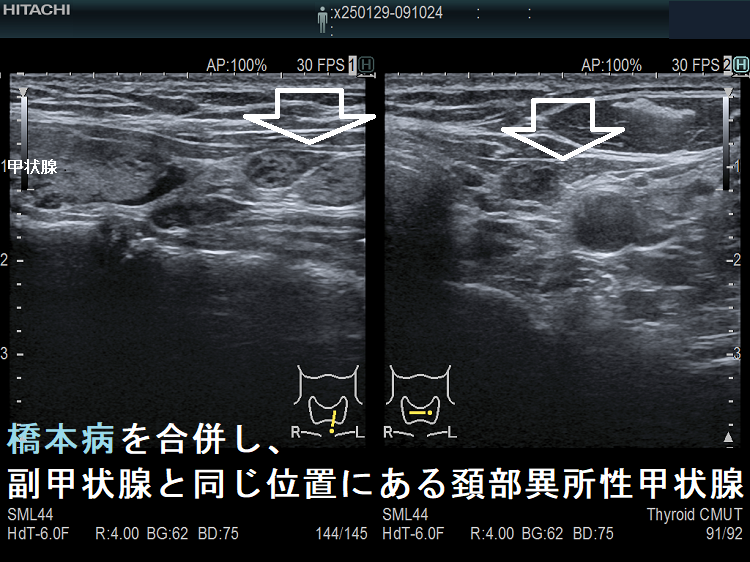

橋本病を合併し、副甲状腺と同じ位置にある頚部異所性甲状腺

橋本病を合併し、副甲状腺と同じ位置にある頚部異所性甲状腺1

橋本病を合併し、副甲状腺と同じ位置にある頚部異所性甲状腺;特徴的な2連構造。甲状腺本体に極めて近い内部構造ですが、やや嚢胞変性が強い印象。癌の転移リンパ節との鑑別が問題になります。

橋本病を合併し、副甲状腺と同じ位置にある頚部異所性甲状腺2

橋本病を合併し、副甲状腺と同じ位置にある頚部異所性甲状腺 ドプラーモード